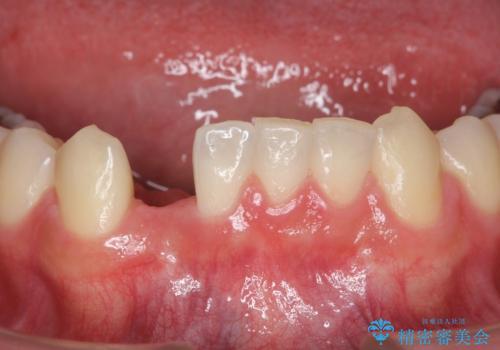

- 下の前歯が1本生まれつき少なかったため、インプラント治療を行いました。

インプラントの前に矯正治療を行い、入れる隙間を確保しました。

唇側の骨増成もしっかり行い、前歯部インプラントによくある、歯茎が下がって見えることもない、審美的なインプラント補綴ができました。